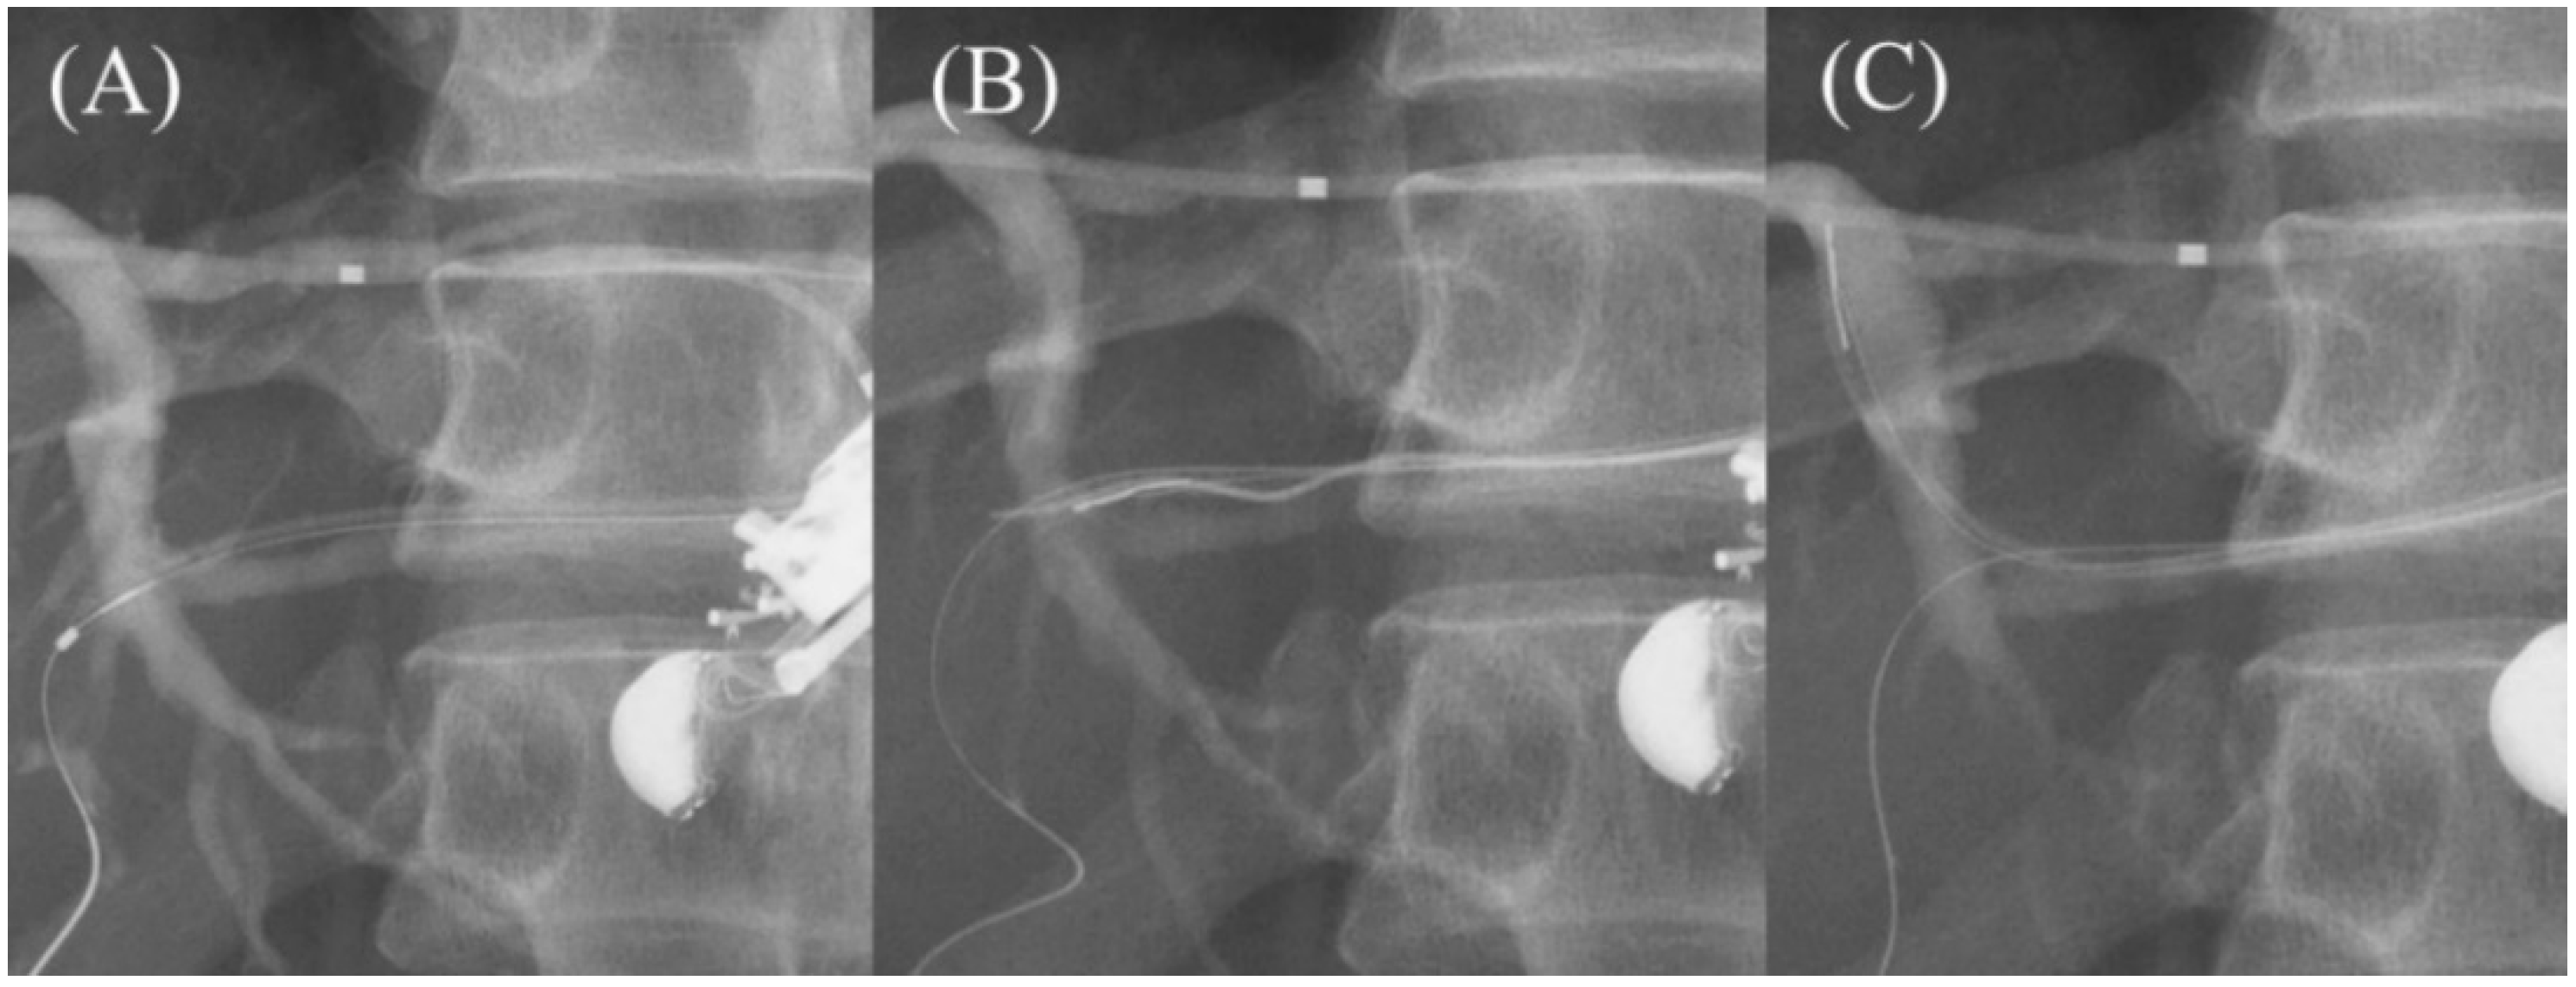

- Shima, Y.; Isayama, H.; Ito, Y.; Hamada, T.; Nakai, Y.; Tsujino, T.; Nakata, R.; Koike, K. Crisscross anchor-stents to prevent metal stent migration during endoscopic ultrasound-guided hepaticogastrostomy. Endoscopy 2014, 46 (Suppl. S1), E563. [Google Scholar] [CrossRef]